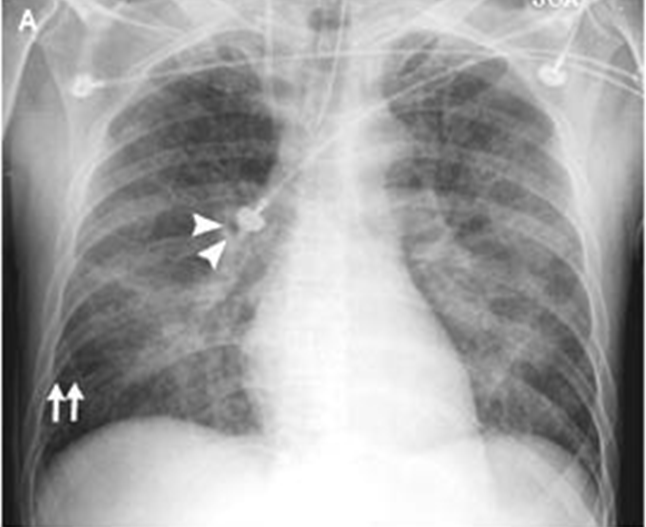

A 51-year-old man who presented with acute anterior myocardial infarction and acute cardiogenic pulmonary edema. Note the enlargement of the peribronchovascular spaces (arrowheads) and the prominent septal lines (Kerley's B lines) (arrows) as well as acinar areas of increased opacity that coalesce into frank consolidations.

interstitial edema causes dyspnea and tachypnea

what is the most likely cause of increased permeability?

C